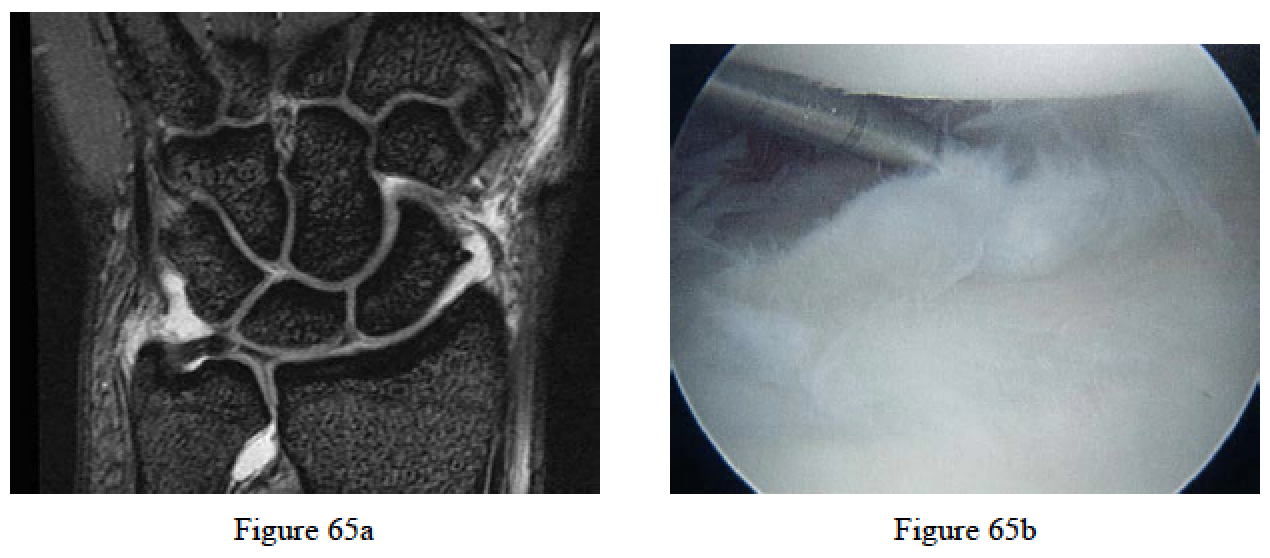

Faber KJ, Iordache S, Grewal R. Magnetic resonance imaging for ulnar wrist pain. J Hand Surg Am. 2010 Feb;35(2):303-7. Review. PubMed PMID: 20141901.

Chen NC, Osterman AL, Culp RW, Chung KC. Wrist arthroscopy. In: Chung KC, Murray PM, eds. Hand Surgery Update 5. Rosemont, IL: American Society for Surgery of the Hand; 2012:159-170.